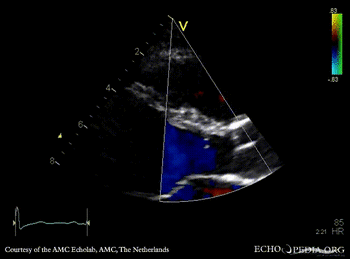

E00737.gif E00738.gif

PSAX with Color Doppler: high velocity flow in LVOT A3CH: subvalvular membrane